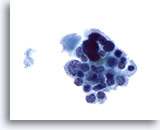

Bij de monsters in deze categorie geldat dat bij resectie in bijna 100% van de gevallen een maligniteit wordt gevonden. Papillair carcinoom is de meest voorkomende maligniteit van de schildklier en heeft specifieke nucleaire kenmerken die eenvoudig zijn vast te stellen bij cytologische monsters. Andere maligniteiten waarvan de diagnose zeer nauwkeurig kan worden vastgesteld op basis van cytologie, zijn onder andere medullaire carcinomen, lymfomen, en metastatische carcinomen. Papillair carcinoom wordt gekenmerkt op ThinPrep door lagen en papillaire clusters van opeengepakte cellen met kernvergroting en molding, poederige chromatine, onregelmatige kerncelmembranen (met name kerngroeven en intranucleaire cytoplasmische inclusies), en kleine maar prominente en vaak eosinofiele nucleoli.[7] Daarentegen wordt medullair carcinoom gekenmerkt door geïsoleerde monomorfe plasmacytoïde cellen, die een hoge kern/cytoplasma-ratio hebben, excentrische kernen en grofkorrelige chromatine met of zonder een prominente nucleolus. Kleine, onopvallende granulen vullen het cytoplasma. Soms lijken de cellen spoelvormig, maar vertonen ze dezelfde nucleaire kenmerken. Lymfomen en metastatische carcinomen van de schildklier komen veel minder vaak voor. Hun cytologische kenmerken hangen af van het type en de plaats van oorsprong.